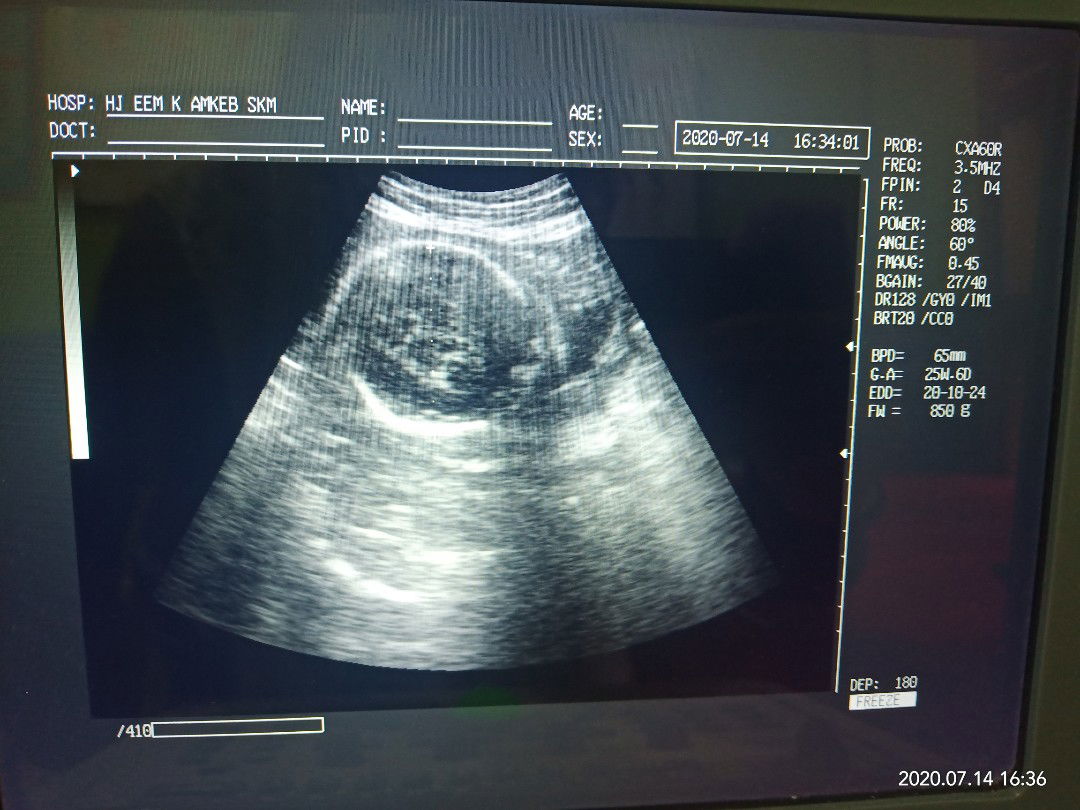

26 minggu

Ada yang sama bun ? 26 minggu, kepala masih di samping ..

Masih bisa muter, aku 32 baru ke bawah

Msh bisa muter bun